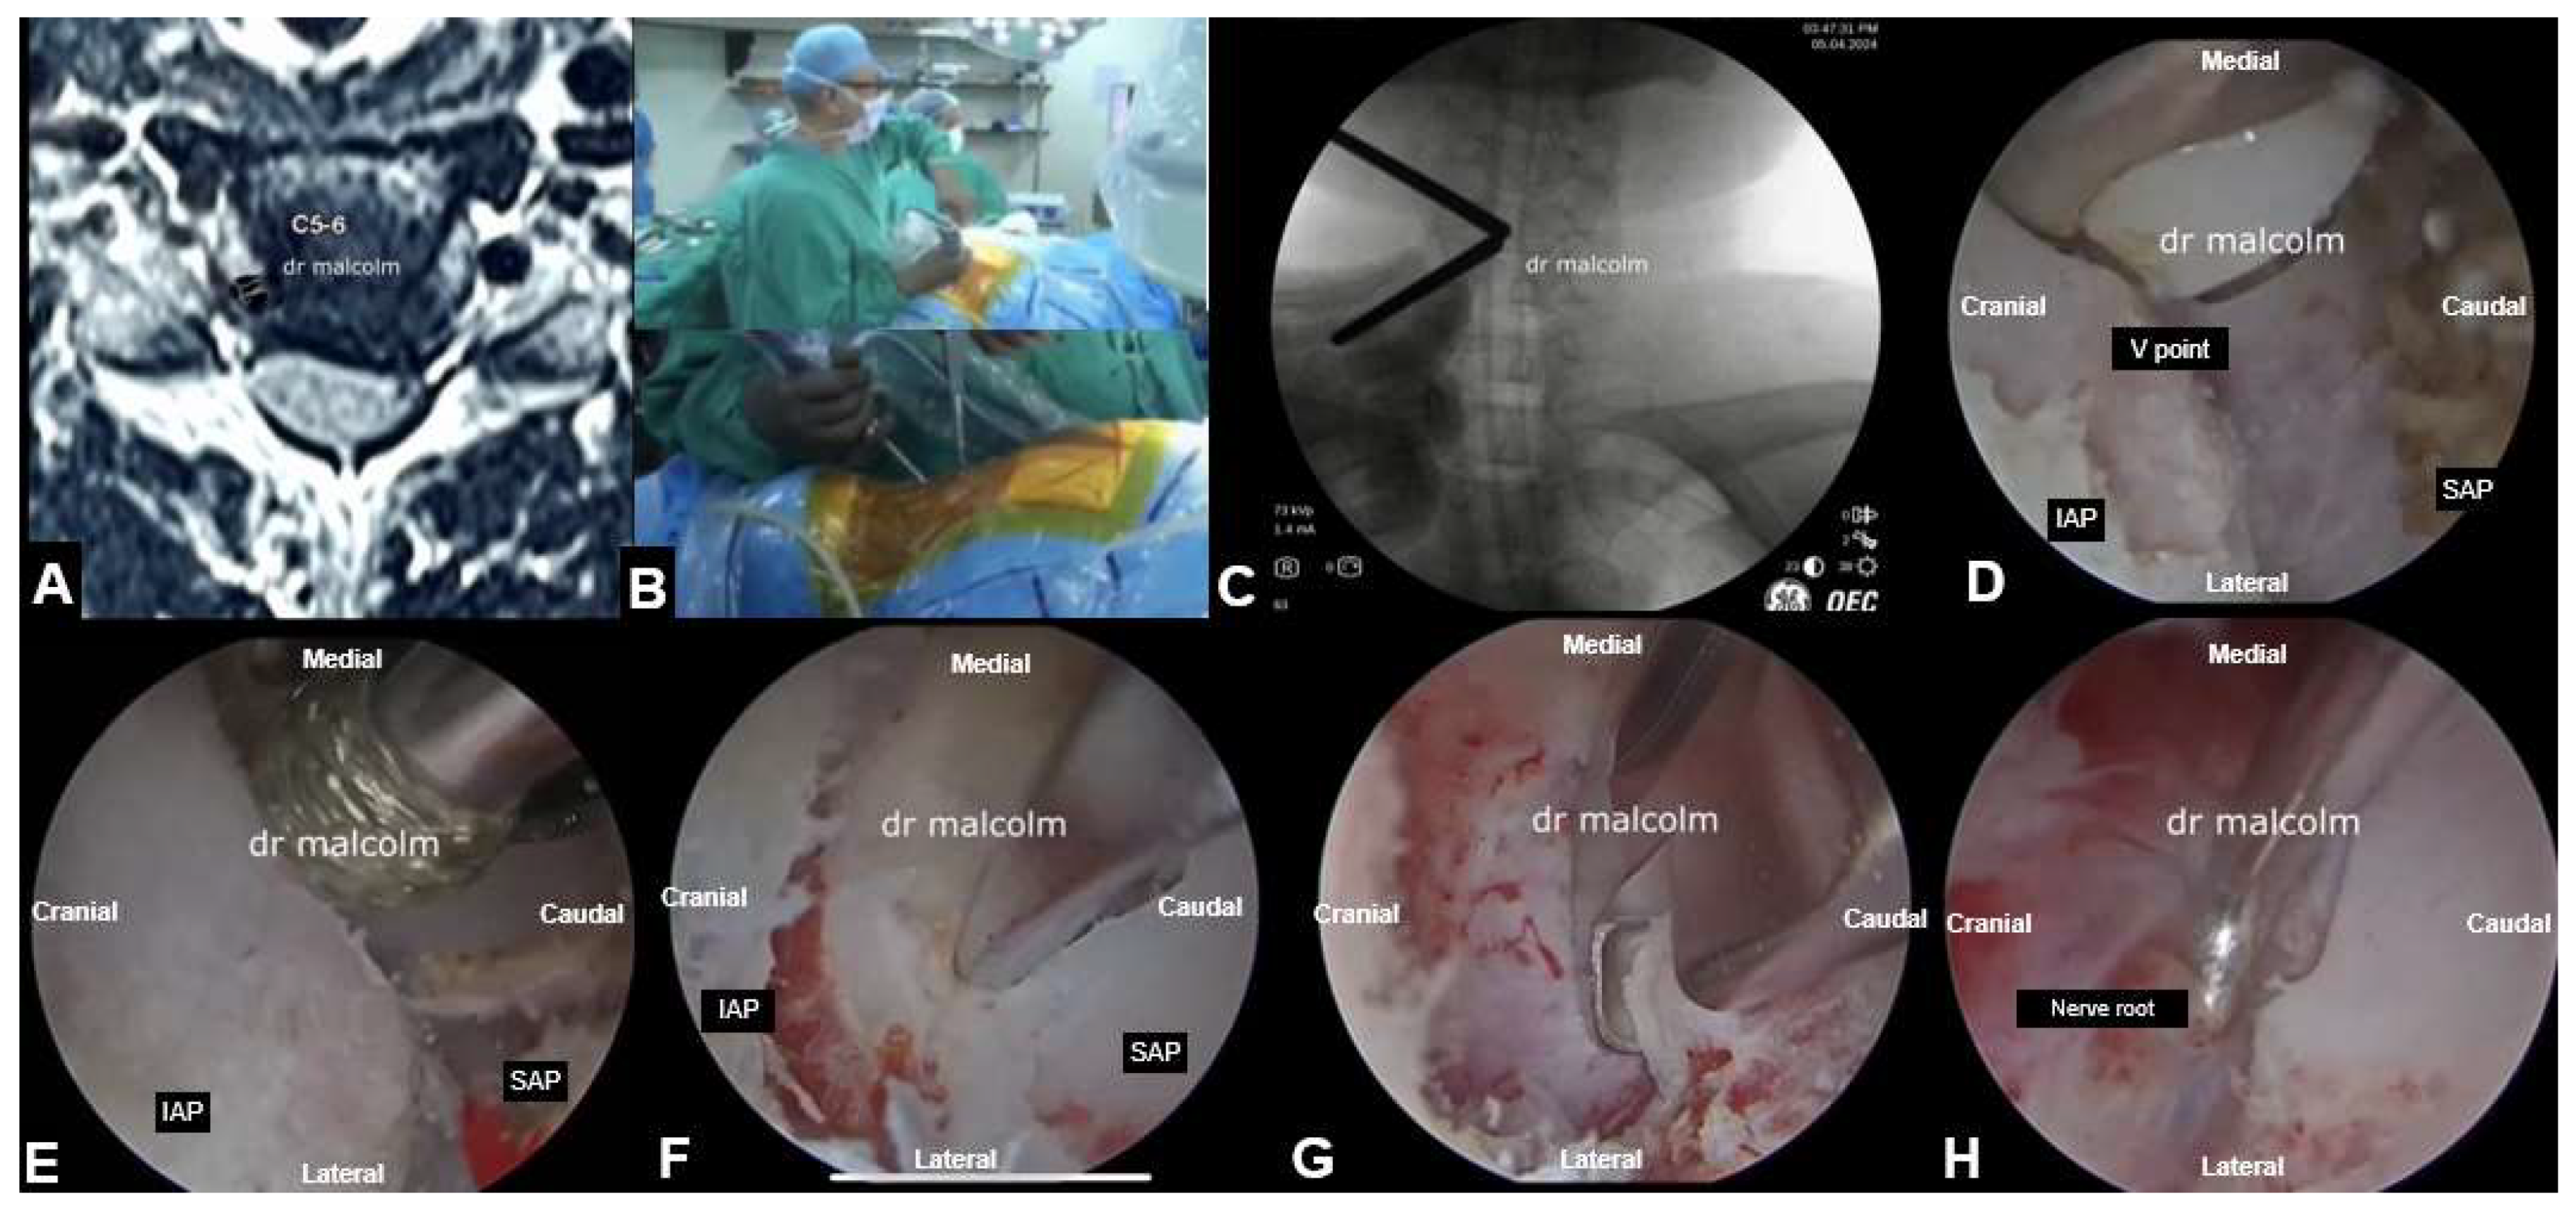

5. Cervical Spine Endoscopy

5.2. Endoscopic Aterior Cevical Dscectomy and Fusion

5.3. UBE Cervical Foraminotomy and Laminectomy